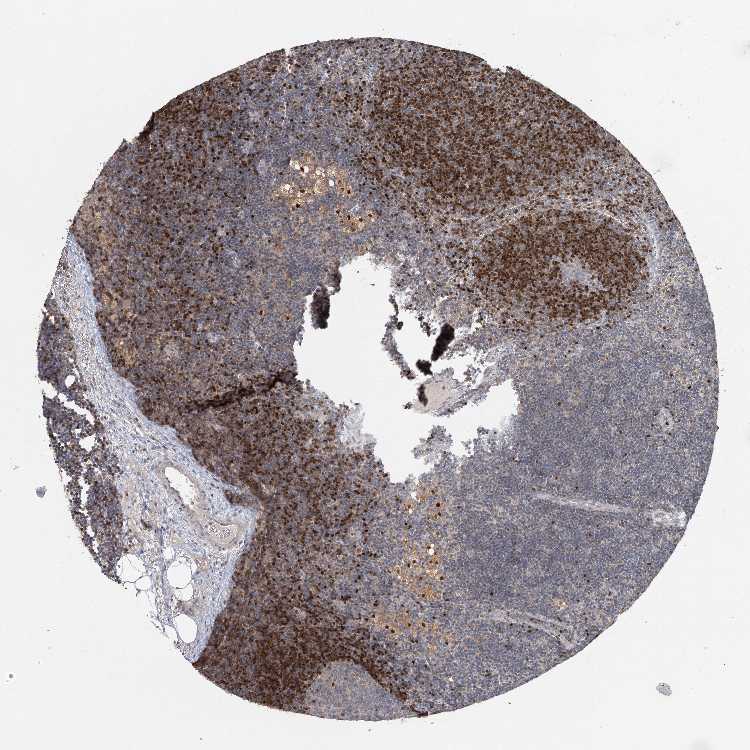

LYMPH NODE - Antibody stainingi

Antibody staining in the annotated cell types in the current human tissue is reported as not detected, low, medium, or high, based on conventional immunohistochemistry profiling in selected tissues. This score is based on the combination of the staining intensity and fraction of stained cells.

Each image is clickable and will lead to virtual microscopy that enables deeper exploration of all samples and also displays staining intensity scores, fraction scores and subcellular localization as well as patient and tissue information for each sample.

Antibody HPA038391Antibody HPA038409Antibody CAB032876

Germinal center cells MediumNot detectedLow

Non-germinal center cells MediumHighMedium